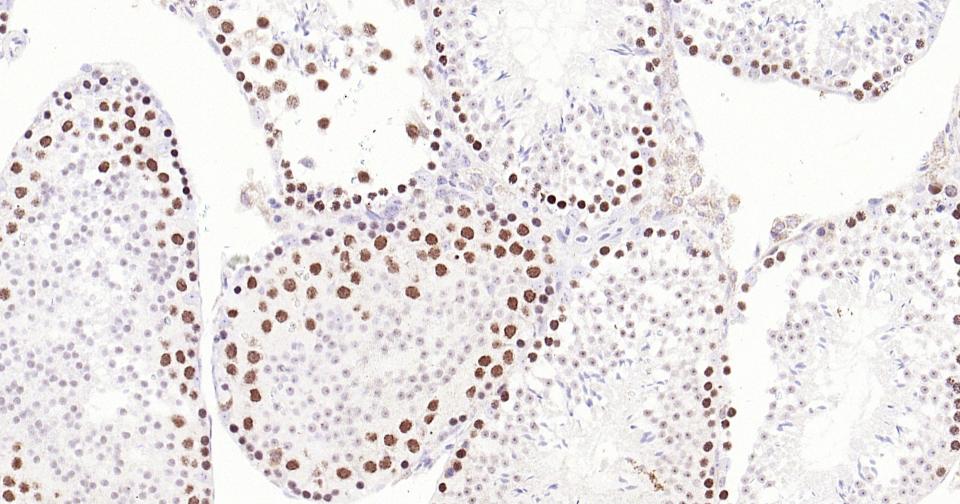

Paraformaldehyde-fixed, paraffin embedded Rat Testicles; Antigen retrieval by boiling in sodium citrate buffer (pH6.0) for 15 min; Antibody incubation with TOP2A Monoclonal Antibody, Unconjugated(bsm-61077R) at 1:200 overnight at 4°C, followed by conjugation to the SP Kit (Rabbit, SP-0023) and DAB (C-0010) staining.

Paraformaldehyde-fixed, paraffin embedded Mouse Testicles; Antigen retrieval by boiling in sodium citrate buffer (pH6.0) for 15 min; Antibody incubation with TOP2A Monoclonal Antibody, Unconjugated(bsm-61077R) at 1:200 overnight at 4°C, followed by conjugation to the SP Kit (Rabbit, SP-0023) and DAB (C-0010) staining.